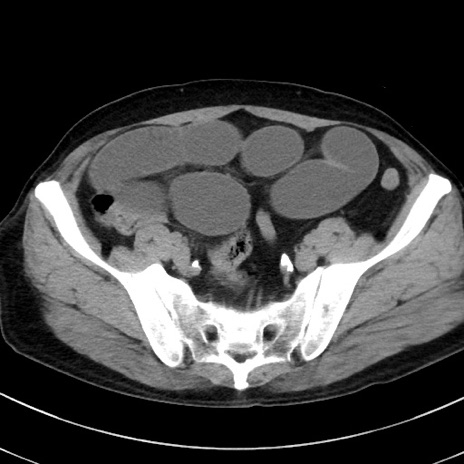

症例38(横断像)

【症例】70歳代 男性

【主訴】腹痛・嘔吐

【現病歴】昨晩より、嘔吐・腹痛あり。今朝になっても嘔吐あり。来院。

【既往歴】心臓バイパス手術、開腹胆摘、腸閉塞

【身体所見】BP 107/71mmHg、HR 116/min、腹部:平坦、軟、下腹部に軽度圧痛あり。反跳痛なし。

【データ】WBC 15100、CRP 0.32